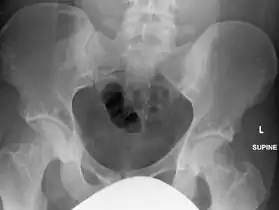

In terms of the diagnosis Osteopoikilosis is radiographically evaluated via the presence of multiple symmetrical circular sclerotic opacities [2]

The radiographic appearance of osteopoikilosis on an X-ray is characterized by a pattern of numerous white densities of similar size spread throughout all the bones. This is a systemic condition. It must be differentiated from blastic metastasis, which can also present radiographically as white densities interspersed throughout bone. Blastic metastasis tends to present with larger and more irregular densities in less of a uniform pattern. Another differentiating factor is age, with blastic metastasis mostly affecting older people, and osteopoikilosis being found in people 20 years of age and younger.

The distribution is variable, though it does not tend to affect the ribs, spine, or skull.[3]

Osteopoikilosis of the hips on CT.